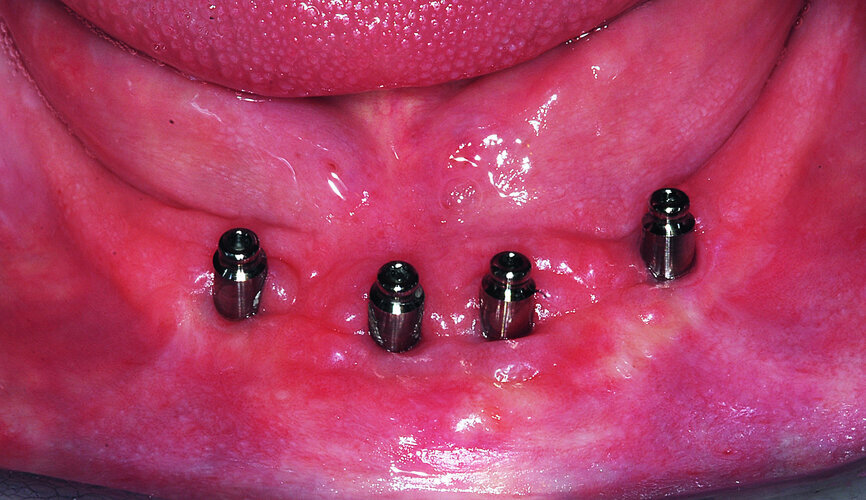

Fig. 20: Four overdenture attachments to support a complete mandibular denture.

After the site was allowed to mature for three months, a midline incision carefully split the narrow band of keratinised tissue to uncover the grafted site and the underlying four implants, which were all covered with a small layer of immature bone. Once fully exposed, each implant was once again fitted with a SmartPeg to assess an ISQ value, which was then compared with the initial values to determine the progress of osseointegration and to confirm implant stability (Figs. 19a & b). The ability to measure stability over time provides invaluable information for the clinician about the health of each implant. A favourable ISQ value imparts a level of confidence and knowledge of when an implant can be loaded and restored. Healing collars were positioned to allow for the soft tissue to be approximated and sutured.

The patient’s initial desire was to help relieve the pain associated with a denture that was not retentive due to the topography of the arch and proximity of the mental nerve to the alveolar crestal bone. The restorative phase continued with the impression phase, and placement of overdenture abutments to secure the denture and prevent pressure on the nerve. The limitation of available keratinised tissue was initially managed to the comfort and cleanability for the patient.

At the time of implant placement, the RFA/ISQ values were recorded. The initial values were actually acceptable if immediate loading was desired (over 70), based upon the excellent stability afforded by the thread design of the implant engaging the buccal and lingual cortex, and apical length into native bone. A two-stage approach was elected due to the large hollow areas in the symphysis, which were grafted and covered with PRF. At three months, the implants were found to be covered with a thin layer of immature bone, and the intramedullary area seemed solid. The second series of measurements were recorded to reflect the status of integration. All values increased significantly, verifying that the process of osseointegration was progressing positively, and loading was appropriate. Overdenture abutments (Meg-Rhein) were secured to each implant, and stainless-steel housings with retentive caps were embedded into the denture.